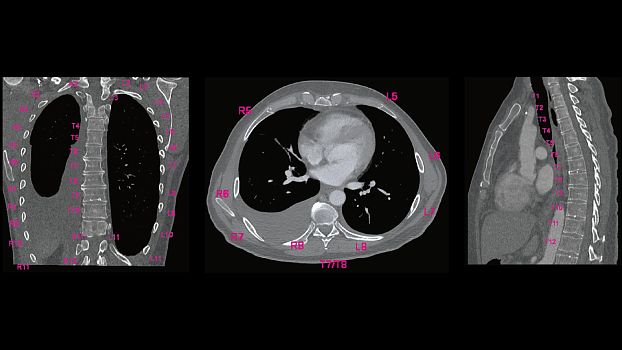

Клинические изображения

SOMATOM go.Up - компьютерный томограф для проведения рутинных и целевых осмотров, лучевой терапии и ангиографии. Система отличается инновационным дизайном рабочего места и полностью обновлённой концепцией сервиса, которая способствует снижению расходов по эксплуатации. Подходит для обследования головного мозга, легких, толстой кишки, сердца, сосудов. Вы можете заказать или купить со склада в наличии компьютерный томограф Siemens SOMATOM go.Up по выгодной цене, от надежного официального дистрибьютора "МСТ", с бесплатной доставкой в любой город по всей России.

SOMATOM go.Up позволяет расширять клинический диапазон и развиваться, достигая существенных результатов. Благодаря использованию высоких технологий система обеспечивает результаты, которые ранее были доступны только на томографах высокого класса. Кроме того, SOMATOM go.Up хорошо подходит для целей лучевой терапии. Благодаря пакету RT Image Suite, установленном на рабочей станции сбора данных, можно без труда выполнять разметку, оценивать изображения и проводить оконтуривание мишеней для лучевой терапии.

SOMATOM go.Up оптимизирует качество изображений и снижает лучевую нагрузку в рутинных неврологических исследованиях. SOMATOM go.Up отличается высокой скоростью сканирования и высоким качеством полученных изображений, что повышает качество диагностики особенно мелких сосудистых структур.

SOMATOM go.Up позволяет проводить скрининговые исследования лёгких и толстой кишки, а также исследования сердца для оценки коронарного кальция. Благодаря субмиллиметровой коллимации SOMATOM go.Up обеспечивает высокое пространственное разрешение, тем самым повышая чувствительность диагностики в онкологии.